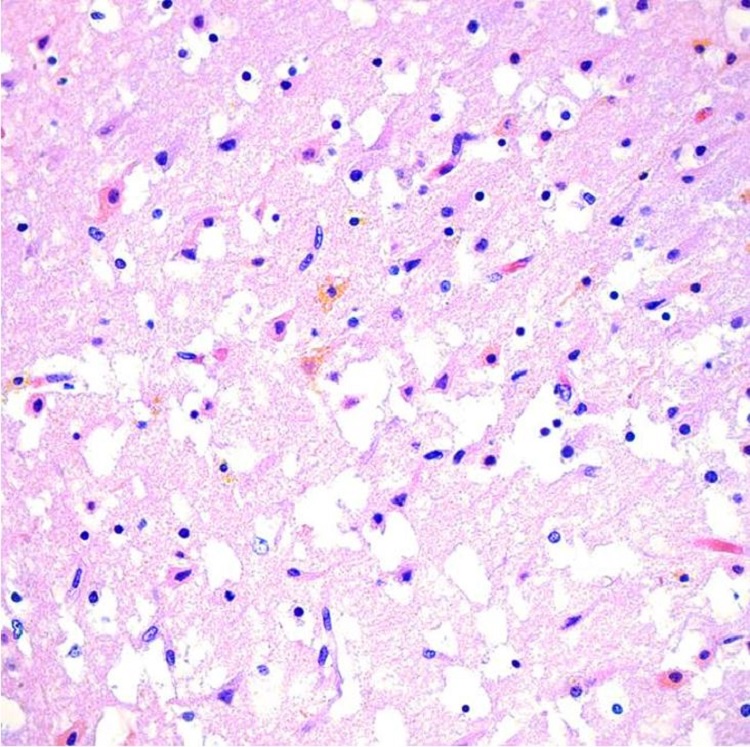

The brain was partially liquefied with extensive bright yellow bilirubin pigment deposition noted in the fresh state (Figure 3A). These pigments were noted most prominently in the basal ganglia and thalamus (Figure 3B) in addition to scattered portions of the brain, including the cerebellum, bilateral occipital lobes, and areas around the lumen of the fourth ventricle. Microscopic examination demonstrated marked distortion of the architecture of the cerebral hemispheres with vacuolation, severe gliosis and numerous neurons with cytoplasmic eosinophilia and nuclear pyknosis, associated with the presence of yellow-orange cytoplasmic pigment (Figure 4). The most extensive damage was noted in the frontal and occipital cortices where there was abundant yellow pigment microscopically, diffuse vacuolation associated with neurons with cytoplasmic eosinophilia and nuclear pyknosis as well as vascular congestion and architectural distortion of the gray and white matter. All these findings were consistent with bilirubin encephalopathy / kernicterus. Gross and microscopic examination of other organs were unremarkable. Liver polymerase chain reaction (PCR) for bacteria, fungus, toxoplasma, adenovirus, parvovirus B19, cytomegalovirus, varicella zoster virus, herpes simplex virus 1 and 2 was negative. Hemophagocytic lymphohistiocytosis (HLH) genetic panel was negative.